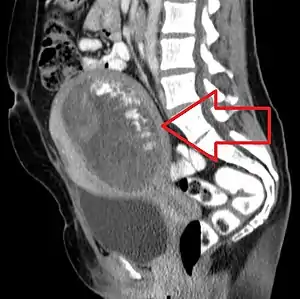

Molar pregnancy seen on CT scan, sagittal view | |

The diagnosis is strongly suggested by ultrasound (sonogram), but definitive diagnosis requires histopathological examination. On ultrasound, the mole resembles a bunch of grapes ("cluster of grapes" or "honeycombed uterus" or "snow-storm").[14] There is increased trophoblast proliferation and enlarging of the chorionic villi, and angiogenesis in the trophoblasts is impaired.[15]